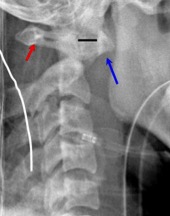

Cervical spine lateral radiograph:

Alignment –

Following 4 lines have to be assessed (figure below):

- Anterior vertebral line: Along anterior aspect of vertebral bodies (Red)

- Posterior vertebral line: Along posterior aspect of vertebral bodies (Blue)

- Spinolaminar line (Yellow)

- Posterior Spinous line (Green)

As mentioned above, normal alotantodental interval (black line in the figure) is 3 mm in adults and 5 mm in children. Flexion and extension radiographs are helpful.